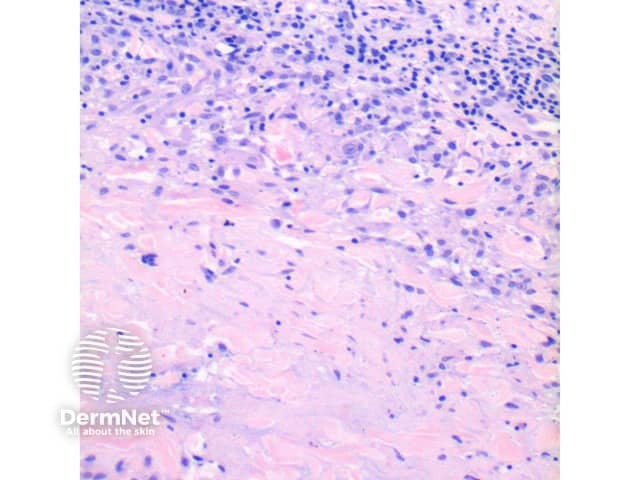

Figure 3